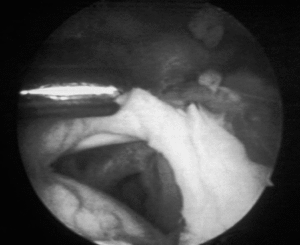

La acromioplastia por vía artroscópica fue descrita por Ellman16 para los estadios II y III de Neer (fig. 3), dando a conocer los resultados preliminares de las primeras descompresiones subacromiales por artroscopia, en las que se reseca la superficie anteroexterna del acromion, se efectúa una bursectomía en los pacientes más jóvenes, y se desinserta el ligamento coracoacromial.

Figura 3. Delimitación del ligamento coracoacromial con dos agujas según la técnica de Ellman.